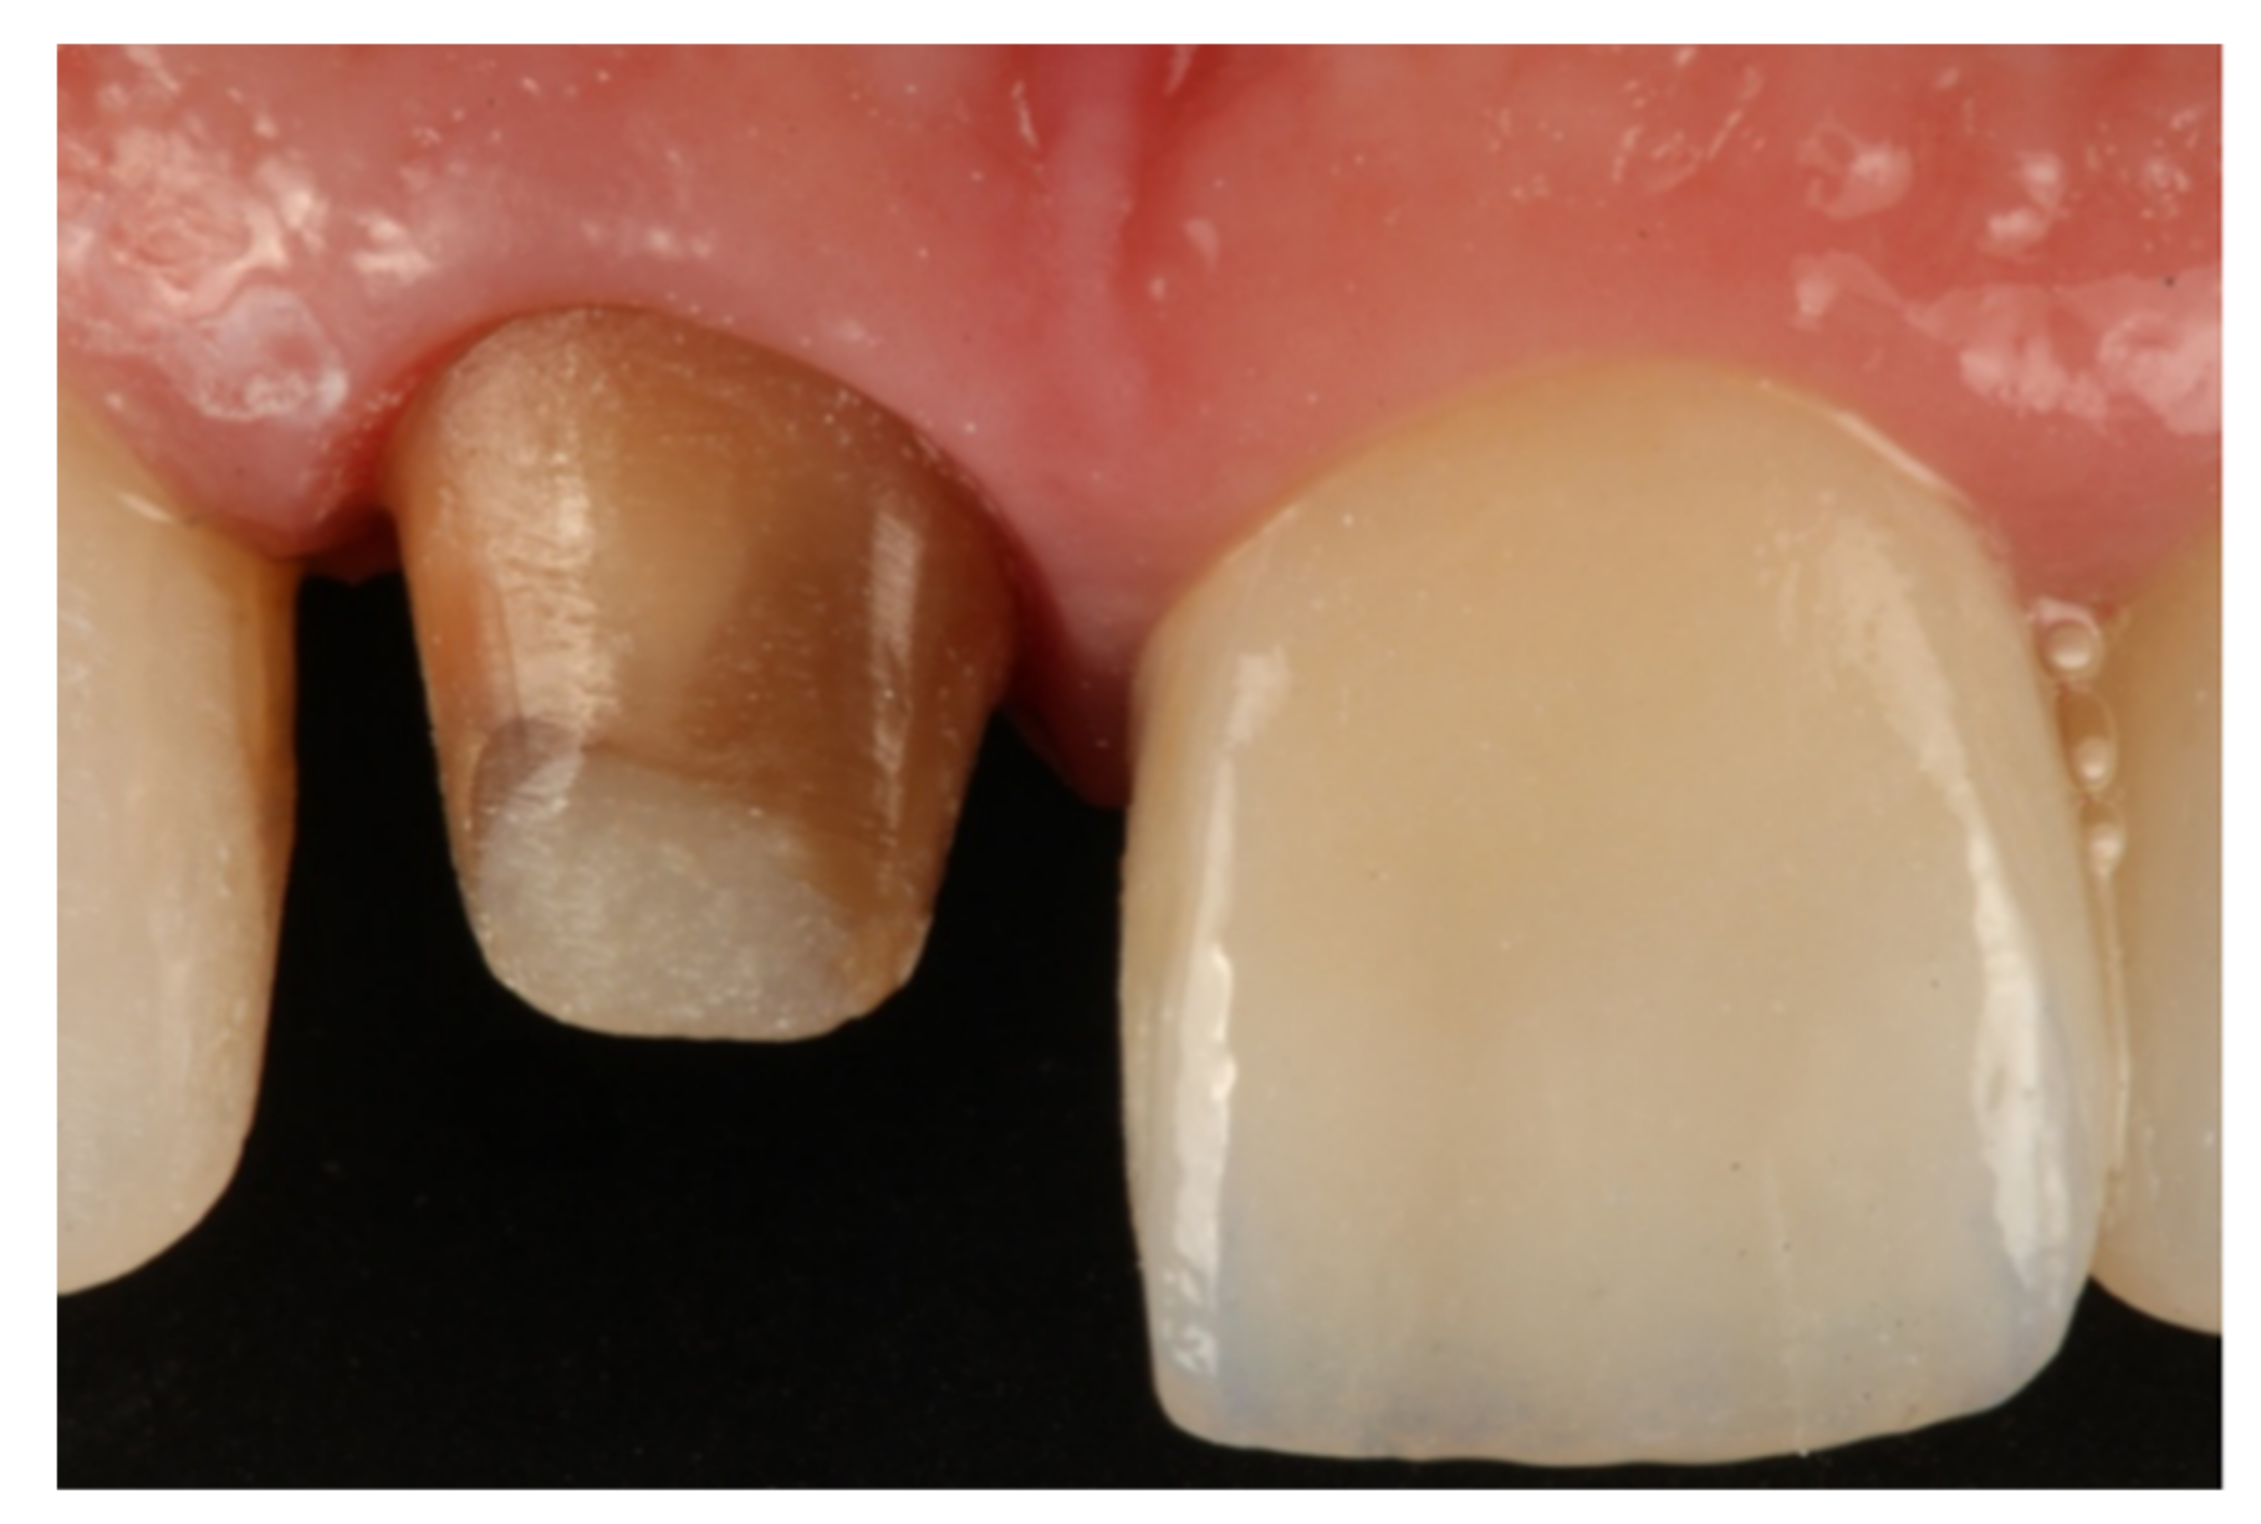

- Agustín-Panadero, R.; Solá-Ruíz, M.F. Vertical preparation for fixed prosthesis rehabilitation in the anterior sector. J. Prosthet. Dent. 2015, 114, 474–478. [Google Scholar] [CrossRef] [PubMed]

- Agustín-Panadero, R.; Serra-Pastor, B.; Fons-Font, A.; Solá-Ruíz, M.F. Prospective Clinical Study of Zirconia Full-coverage Restorations on Teeth Prepared with Biologically Oriented Preparation Technique on Gingival Health: Results After Two-year Follow-up. Oper. Dent. 2018, 43, 482–487. [Google Scholar] [CrossRef] [PubMed]